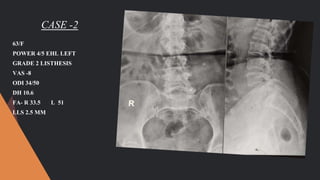

CASE -2

63/F

POWER 4/5 EHL LEFT

GRADE 2 LISTHESIS

VAS -8

ODI 34/50

DH 10.6

FA- R 33.5 L 51

LLS 2.5 MM